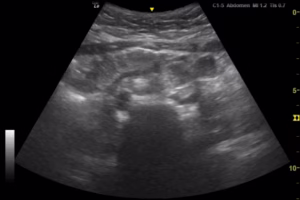

#3 [A]ppendicitis: Is there a non-compressible, blind-ended, large (diameter >6 mm), tubular structure in the RLQ at the point of maximal tenderness, yes or no? These findings are specific for acute appendicitis (Figure 5).

Figure 5. Point of care ultrasound (POCUS) findings with anterior-posterior appendiceal diameter greater than 6mm in longitudinal (A) and transverse (B) views.

Transabdominal Scanning Technique: Either the linear or curvilinear transducer can be used to evaluate appendicitis. While the linear transducer is generally preferred, the curvilinear transducer may provide better visualization through increased depth in patients with greater body mass indices. The ideal transducer placement for identification of the appendix is on the RLQ, particularly at the point of maximal pain or tenderness to palpation. The transducer should be oriented in the transverse plane and the transducer marker should be pointed to the patient’s right shoulder. The anatomic landmarks for identifying the appendix are the psoas muscle and the iliac vessels. The psoas muscle can be seen on the left side of the screen (laterally on the patient) and the iliac vessels will be on the right side of the screen (medially on the patient). The appendix lies anterior to the iliac vessels and will be closer to the top of the screen. The appendix can be differentiated from other structures as it is a blind-ended, non-compressible tubular structure without peristalsis or Doppler color flow.